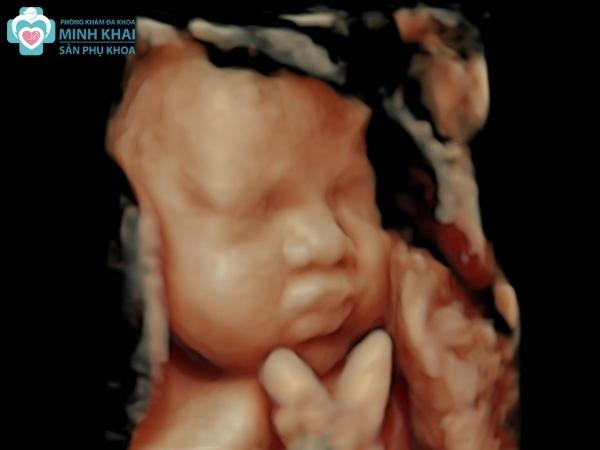

Siêu âm thai 3D cho phép thấy được hình ảnh chụp thật 3 chiều của em bé chứ không phải chỉ là những mặt cắt như 2D. Không chỉ vậy hình ảnh 3D còn được chụp với các góc độ khác nhau. Nó cho thấy rõ được toàn bộ cấu trúc thai nhi chi tiết đến từng đường nét cũng như nội soi rõ các mô nội tạng, tim, hệ mạch máu,...

Vậy nên công cụ siêu âm 3D rất đắc lực trong việc phát hiện bất thường, dị tật bẩm sinh của thai nhi. Chúng cho phép chẩn đoán chính xác các vấn đề về não nhờ phân tích các “điểm mềm” tồn tại trong hộp sọ của thai nhi ở tuần thứ 15 đến 17 thai kỳ.